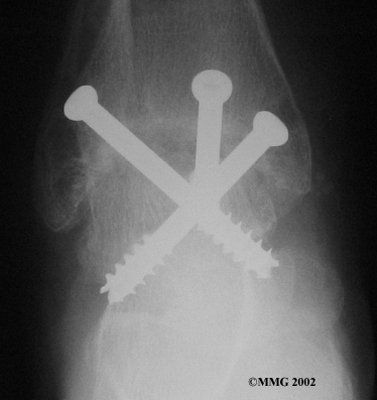

It is important when the surfaces are removed that the angles of the cut surfaces are correct. When the tibia is brought against the talus, the foot should be at a right angle to the lower leg. Once the cuts are made the bones must be held in place while they fuse. This can be done using large metal screws and metal plates if necessary. The screws are usually under the skin and are not removed unless they begin to rub and cause pain.

Inserting the screws

After ankle fusion, the physical therapists at FYZICAL Plainfield can help you learn to walk smoothly and without a limp. Although time needed for recovery varies among patients, an ankle brace will typically replace your cast after eight to 12 weeks. Your surgeon will take X-rays frequently to see if the bones are fusing together. You will probably need to use crutches during the time you wear the cast. As the fusion grows stronger, you will begin to put more weight on your foot when walking.